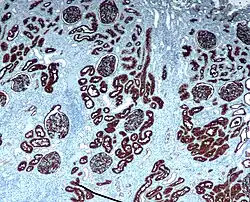

CD10 immunohistochemical staining of normal kidney. CD10 stains the proximal convoluted tubules and glomeruli. -